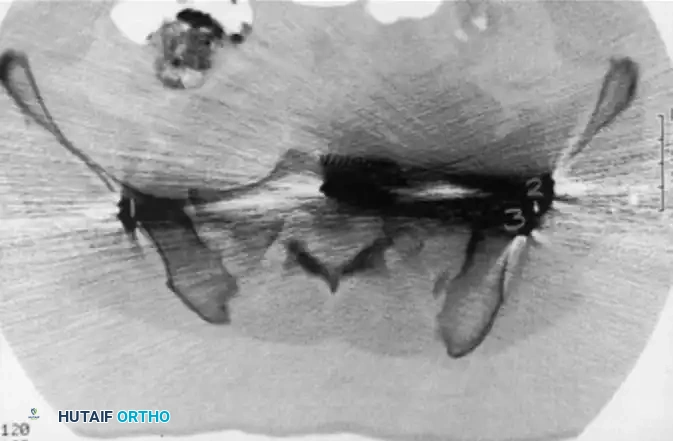

Image

CT scan demonstrating a recessed sacral ala (solid arrows) relative to the dense iliac bone adjacent to the sacroiliac joint—the iliac cortical density (ICD) (open arrow). Nerve roots are surrounded by fat within these recessed alae.